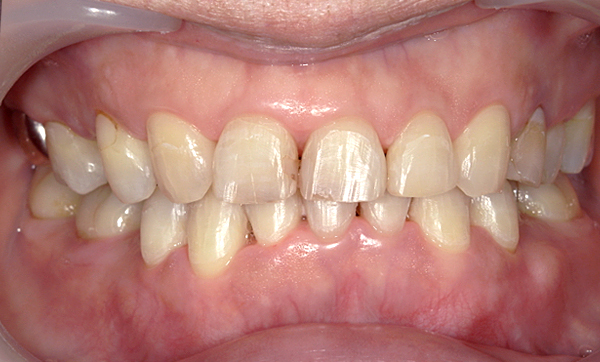

症例_016 上下顎の部分矯正

治療期間:8ヶ月金額:48万円+税50代女性八重歯捻転歯前歯のガタガタ